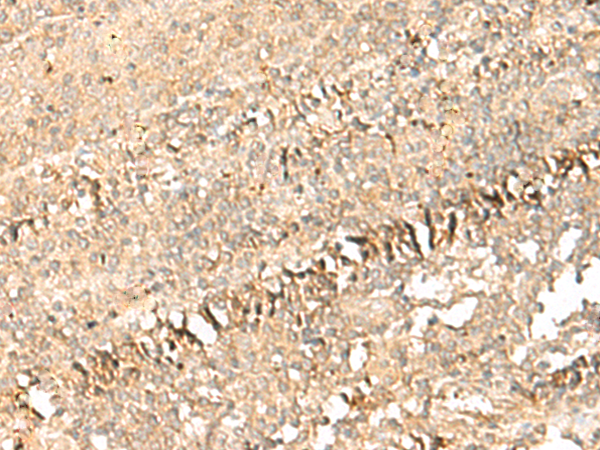

分类: 科研抗体货号: P09962别名:应用: IHC反应种属: Human, Mouse